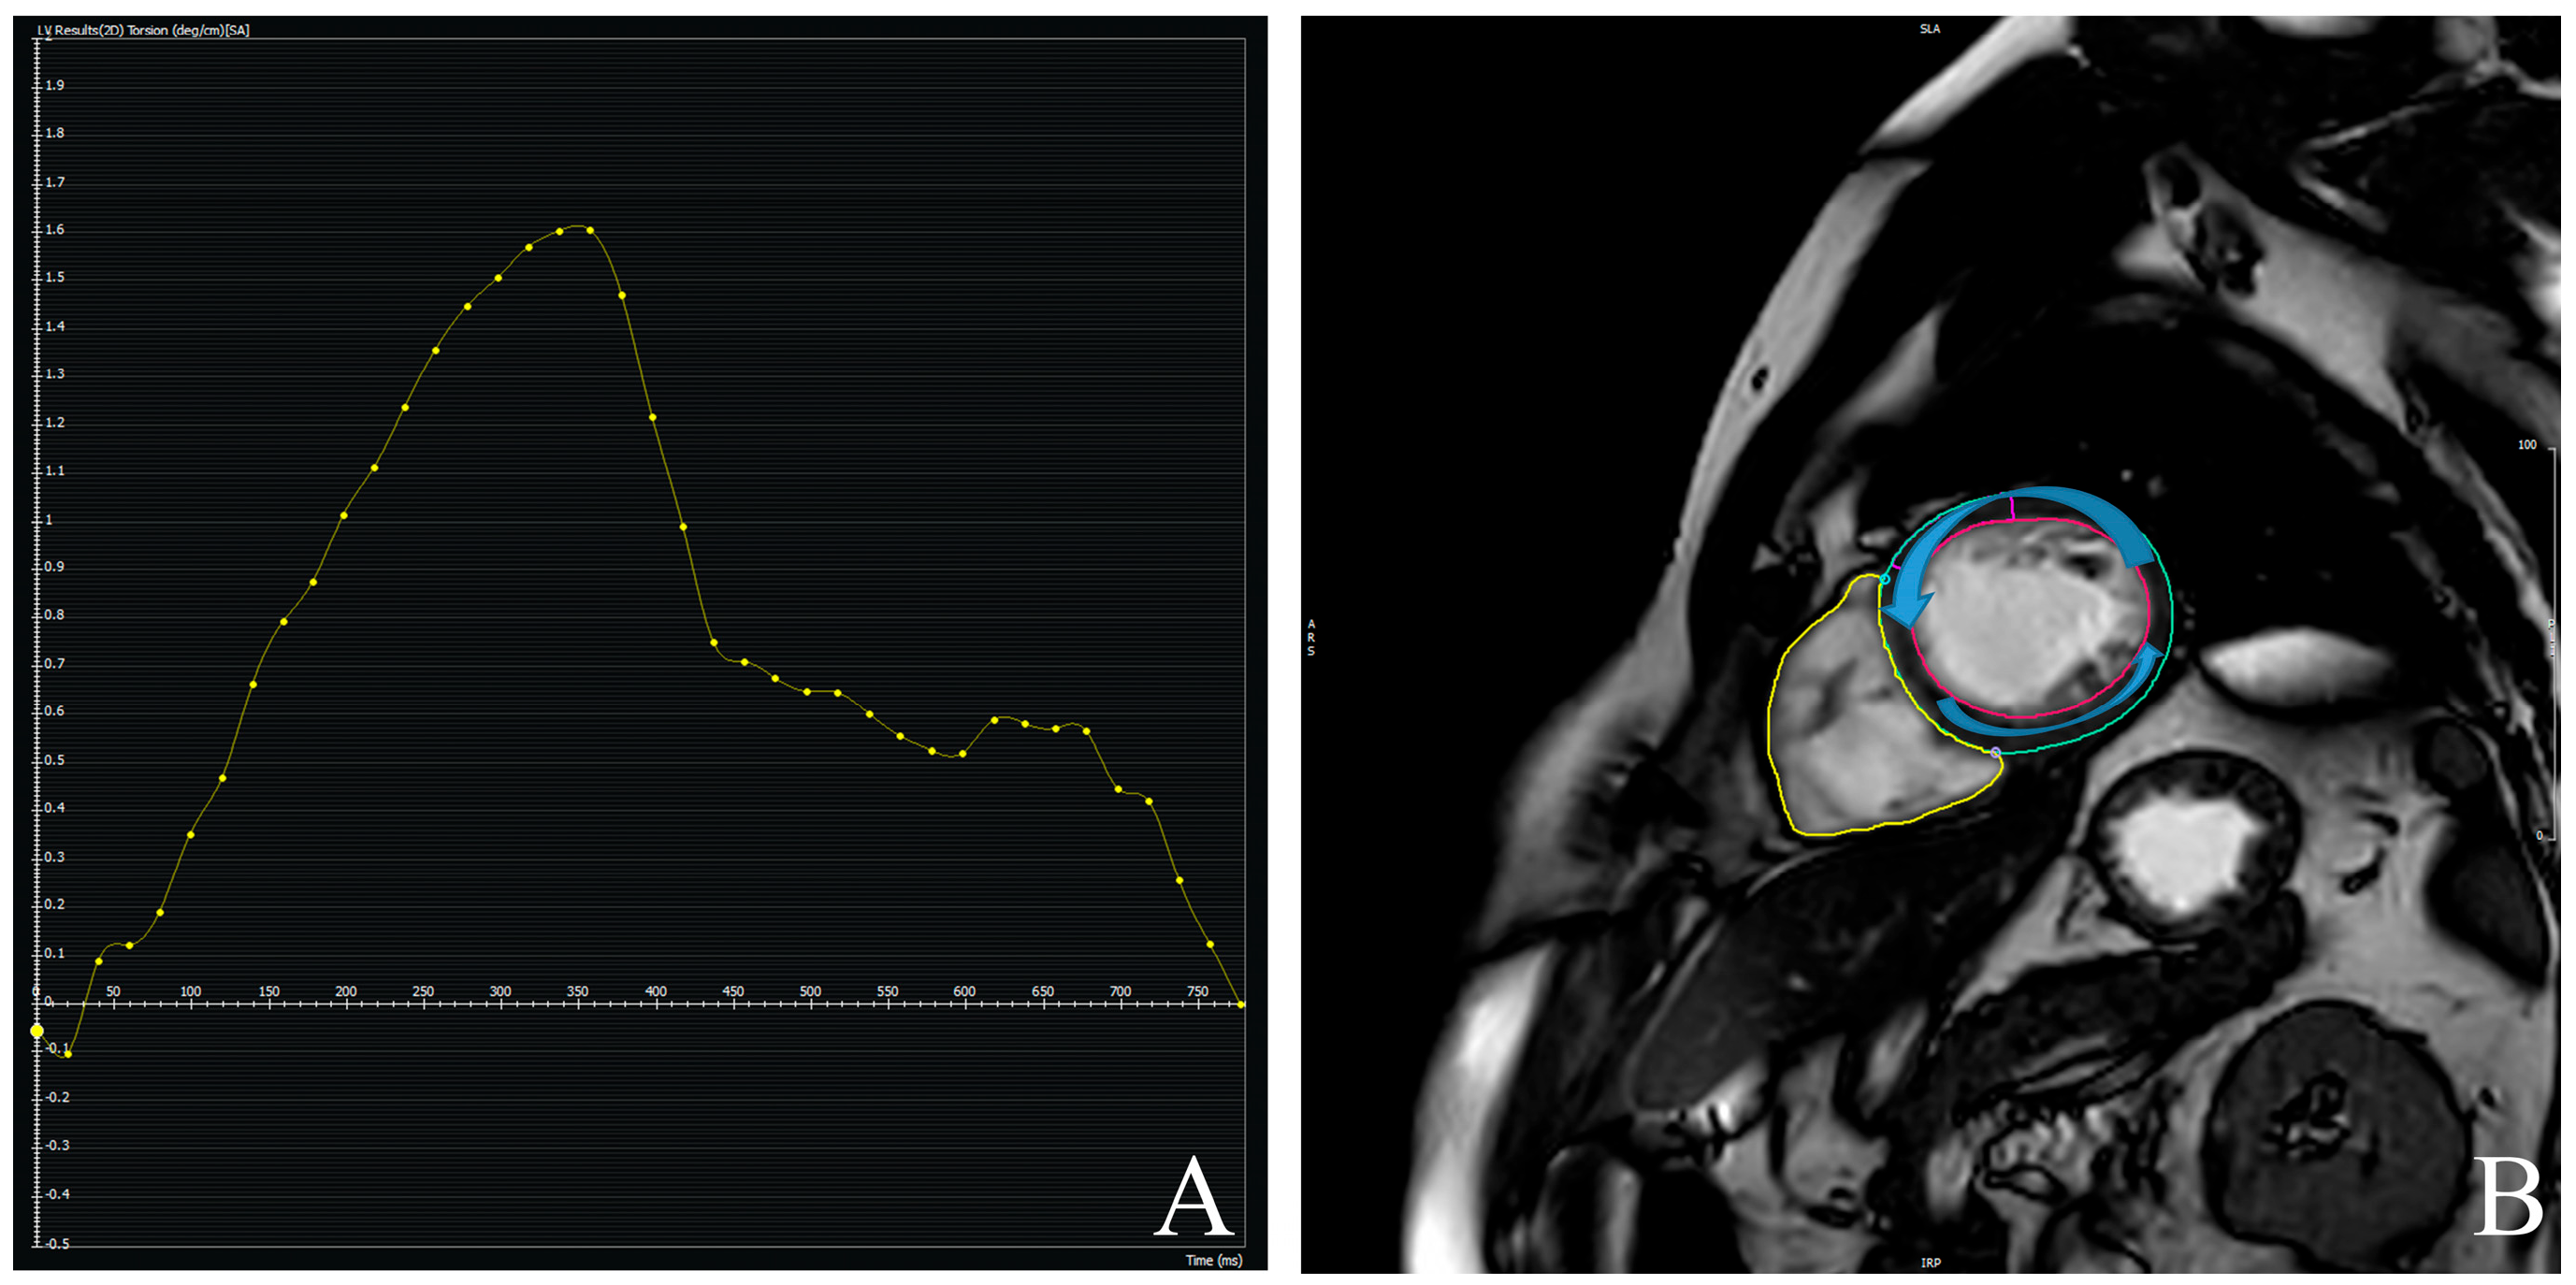

3.4. Prognostic Value of CMR-Derived LV-Torsion

- Young, A.A.; Cowan, B.R. Evaluation of left ventricular torsion by cardiovascular magnetic resonance. J. Cardiovasc. Magn. Reson. 2012, 14, 49. [Google Scholar] [CrossRef]

| 1.04 (0.19) | 1.95 (0.22) | <0.001 |